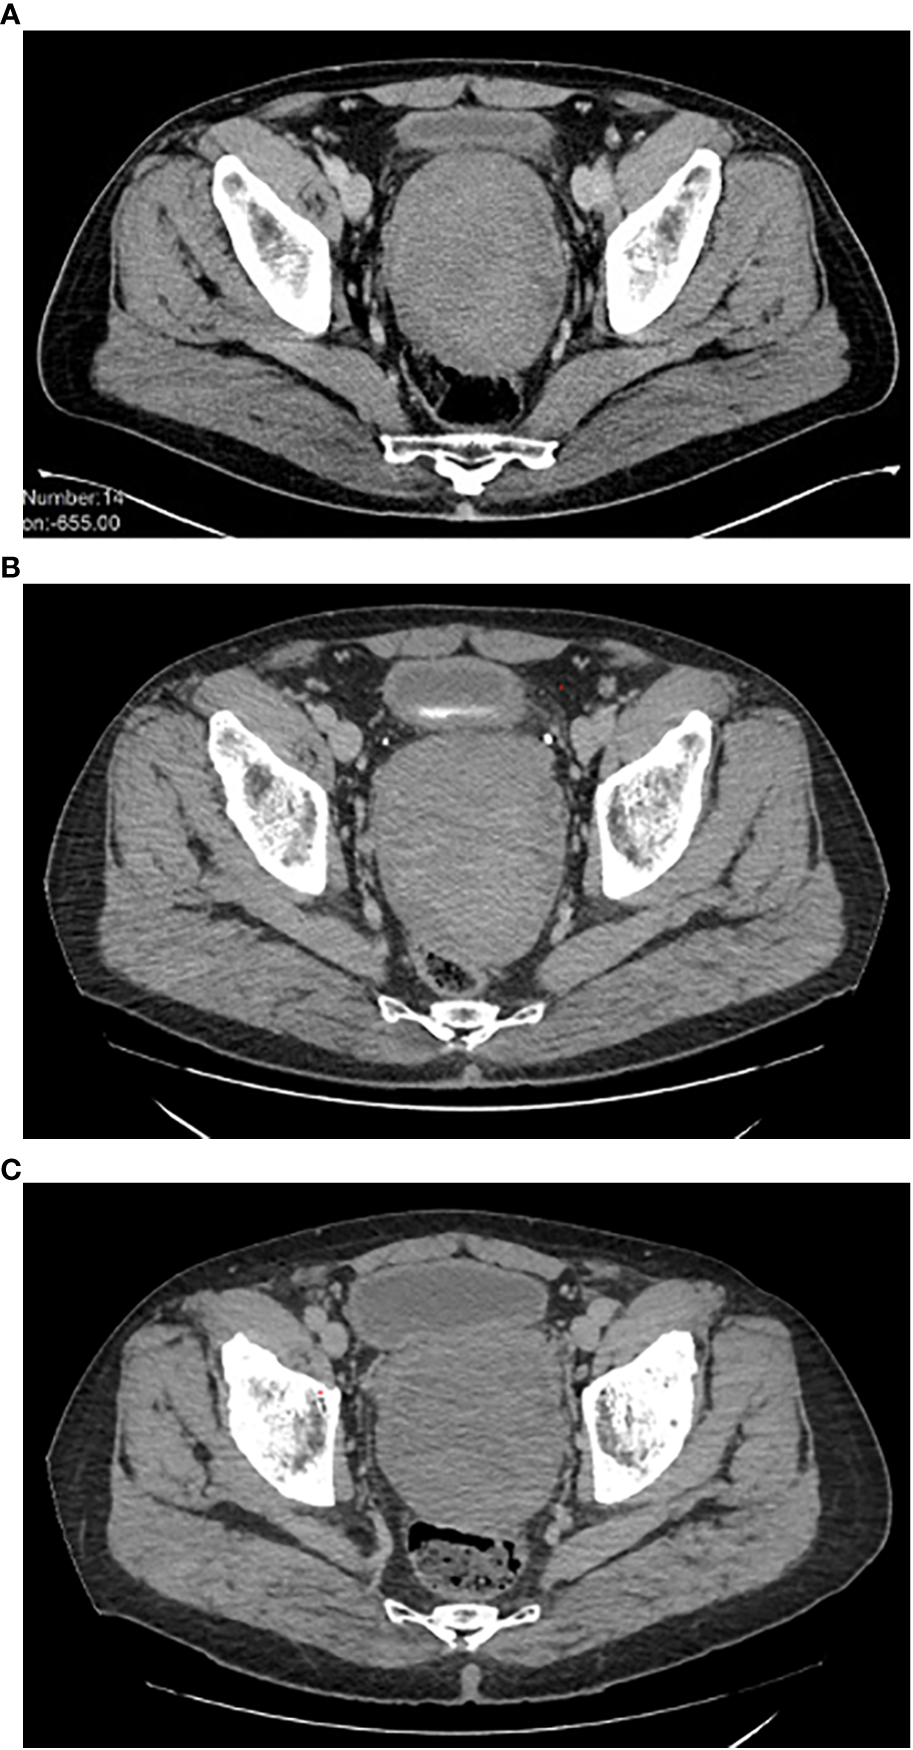

The initial size of the perineal lesion was 10x9x13 cm (Figure 1A), with a disease stability lasting about 12 months during watchful waiting. However, in December 2019, the mass began to increase in size (12x10x14 cm).

Figure 1 (A-C) Disease imaging (CT-scan). (A) Disease status at diagnosis. (B) Disease status at the time of bicalutamide start. (C) Disease status after 32 months of bicalutamide therapy. CT, computed tomography.

Therefore, a systemic treatment with an aromatase inhibitor (letrozole, 30 mg daily p.o.) was started. After three months of treatment (March 2020), the patient underwent a new CT scan, which documented further disease progression (Figure 1B). Low back pain also worsened, with an increasing need for painkiller administration.

The case was discussed in a multidisciplinary setting: considering the risk and the future implications of a mutilating surgery, another medical attempt was made. Given the positive receptor status, a double androgenic blockade was proposed, but patient refused due to foreseeable side effects. He was then put on bicalutamide alone at the dose of 150 mg daily p.o. in April 2020, with a prompt substantial reduction of low back pain and a significant quality-of-life improvement. Periodic (every 3-4 months) imaging assessments with abdominal and thoracic CT scan were performed, documenting a substantial radiological stability, confirmed at the last follow-up of December 2022, 32 months since the start of bicalutamide therapy (Figure 1C).